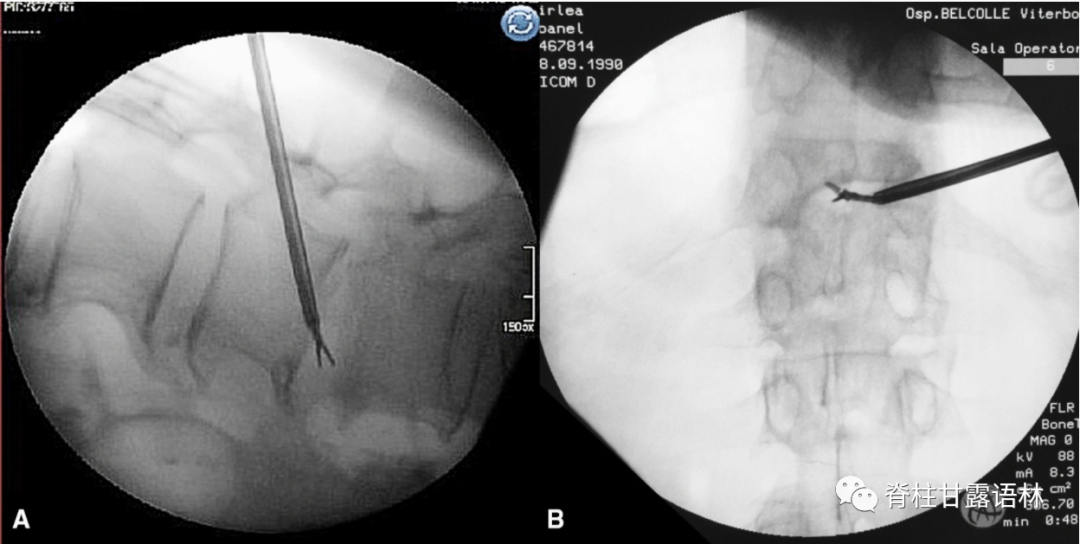

图2 活检过程透视图。A 侧位透视显示钳子到达的深度,可以选择对椎间盘或椎体终板进行取样。B 正位透视情况,活检钳可以越过椎体中线,甚至到达穿刺对侧区域。